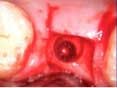

Case 1: Osteotome sinus lift with simultaneous implant placement

A 53-year-old female with a medical history of hypothyroidism, seasonal allergies, and asthma taking Synthroid and Singula presented to my office with pain in No. 3, failed root canal therapy, and a fracture. The tooth was deemed hopeless and extraction and implant placement was treatment planned. Under local anesthesia, tooth No. 3 was sectioned into three pieces and extracted. The sockets were debrided, filled with gel foam, and closed with chromic gut sutures. Healing was uneventful. The patient did not return for two years for follow-up. A CT scan was taken, which confirmed that approximately5 mm of bone remained below the floor of the sinus. After reviewing the options with the patient, a treatment plan of an internal sinus lift (osteotome), bone graft, platelet-rich fibrin (PRF) and simultaneous implant placement was agreed upon. Under local anesthesia, a full thickness flap with two vertical releasing incisions was performed at tooth No. 3 site. A trephine bur was used to a depth of 4 mm. An osteotome was then employed to infracture the bone core, which remained attached to the Schneiderman membrane. A bone graft consisting of DFDBA, anorganic bovine bone, and PRF was used in the osteotomy to increase the vertical bone height using sequential osteotomes. After sufficient elevation, a 7x9 tapered implant was placed on low speed to 50% of the implant depth. The remaining placement of implant was done with a hand torque on 50 ncm to allow for further expansion of the alveolar housing. A healing abutment was placed using the principles of platform switching. Healing was uneventful, and integration was successful.

Case 1: Implant and osteotome bone graft through the socket with Southern Implant